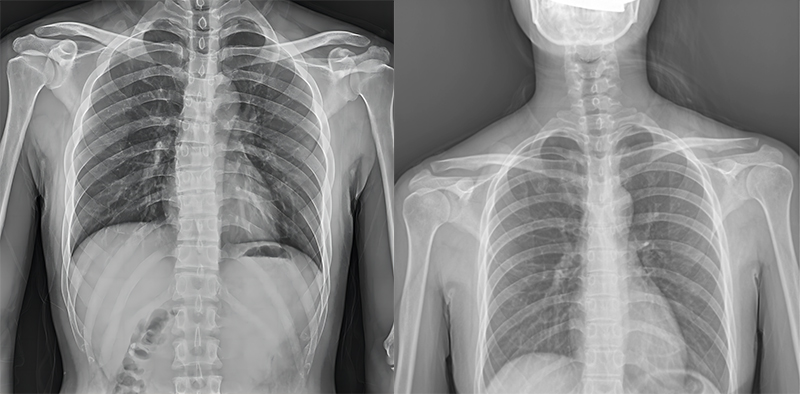

百微米DR與普通像素尺寸DR的影像對比

以胸部攝影為例,通過對比百微米大平板與普通像素尺寸平板的影像,可以看到百微米影像對比度適中,圖像清晰度更高,成像細節(jié)更加豐富。在胸部影像顯示中肺門影結(jié)構(gòu)、肺紋理等細節(jié)展示更清楚,兩側(cè)膈肌邊緣、心臟、縱隔邊緣清晰銳利顯示,在影像中都可以清晰地顯示胸部細微結(jié)構(gòu),滿足臨床診斷要求。